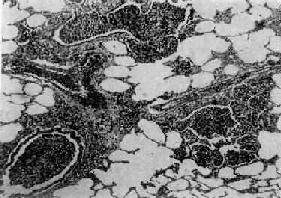

图9-15 大叶性肺炎 肺泡腔内充满纤维素性渗出物,纤维素丝穿过肺泡间孔,使相邻肺泡内的纤维素网互相连接

二、肺炎肺炎(pneumonia)通常是指肺的急性渗出性炎症,为呼吸系统的多发病、常见病。据世界卫生组织调查,肺炎死亡率占呼吸系统急性感染死亡率的75%。在我国,各种致死病因中,肺炎占第5位。肺炎可由不同的致病因子引起,根据病因可将肺炎分为感染性(如细菌性、病毒性、支原体性、真菌性和寄生虫性)肺炎,理化性(如放谢性、吸入性的类脂性)肺炎以及变态反应性(如过敏性和风湿性)肺炎。由于致病因子和机体反应性的不同,炎症发生的部位、累及范围和病变性质也往往不同。炎症发生于肺泡内者称肺泡性肺炎(大多数肺炎为肺泡性),累及肺间质者称间质性肺炎。病变范围以肺小叶为单位者称小叶性肺炎,累及肺段者称节段性肺炎,波及整个或多个大叶者称大叶性肺炎。按病变性质可分为浆液性、纤维素性、化脓性、出血性、干酪性、肉芽肿性或机化性肺炎等不同类型。 (一)细菌性肺炎 1.大叶性肺炎 大叶性肺炎(lobar pneumonia)主要是由肺炎链球菌感染引起,病变起始于肺泡,并迅速扩展至整个或多个大叶的肺的纤维素性炎。多见于青壮年,临床表现为骤然起病、寒战高烧、胸痛、咳嗽、吐铁锈色痰、呼吸困难,并有肺实变体征及白细胞增高等。大约经5~10天,体温下降,症状消退。 【病因和发病机制】 95%以上的大叶性肺炎由肺炎链球菌引起,尤以Ⅲ型者毒力最强。此外,肺炎杆菌、金黄色葡萄球菌、溶血性链球菌、流感嗜血杆菌也可引起。受寒、疲劳、醉酒、感冒、麻醉、糖尿病、肝、肾疾病等均可为肺炎的诱因。此时,呼吸道的防御功能被削弱,机体抵抗力降低,易发生细菌感染。细菌侵入肺泡后在其中繁殖,特别是形成的浆液性渗出物又有利于细菌繁殖,并使细菌通过肺泡间孔或呼吸细支气管迅速向邻近肺组织蔓延,从而波及整个大叶,在大叶之间的蔓延则系带菌渗出液经叶支气管播散所致。 【病理变化】 病变一般发生在单侧肺,多见于左肺下叶,也可同时或先后发生于两个以上肺叶。病变基本特征是肺的微循环障碍。由于毛细血管通透性增高,大量纤维蛋白原渗出于肺泡,使肺组织大面积广泛实变。病变早期,肺叶充血、水肿,肺泡腔内有大量浆液性渗出物,混有少数红细胞、中性粒细胞和巨噬细胞,并含有大量细菌。1~2天后,即有大量纤维蛋白原渗出,肺泡腔内充满混有红细胞、中性粒细胞、巨噬细胞的纤维素性渗出物,纤维素丝可穿过肺泡间孔与相邻肺泡中的纤维素网相连(图9-15)。病变肺叶质实如肝,明显肿胀,重量增加,呈灰白色(图9-16)。如血管损伤较重、出血较多,外观可呈红色。大约经5~10天,炎症消退,细菌被吞噬细胞吞噬清除,渗出物被溶解,或经淋巴管吸收或被咳出。大叶性肺炎时,肺组织常无坏死,肺泡壁结构也未遭破坏,愈复后,肺组织可完全恢复其正常结构和功能。